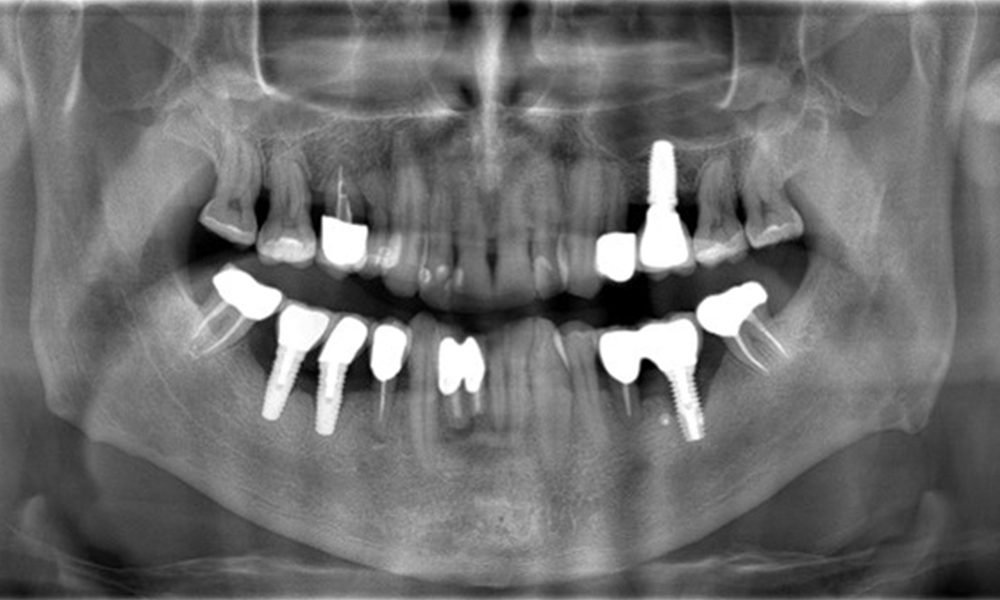

The X-ray images show the progression of bone loss. OPG from 29.06.2020 (left) and OPG from 26.02.2024 (right).

OPG: 26/02/2024 Dental X-ray: 18/01/2024

The X-ray images show the progression of bone loss.